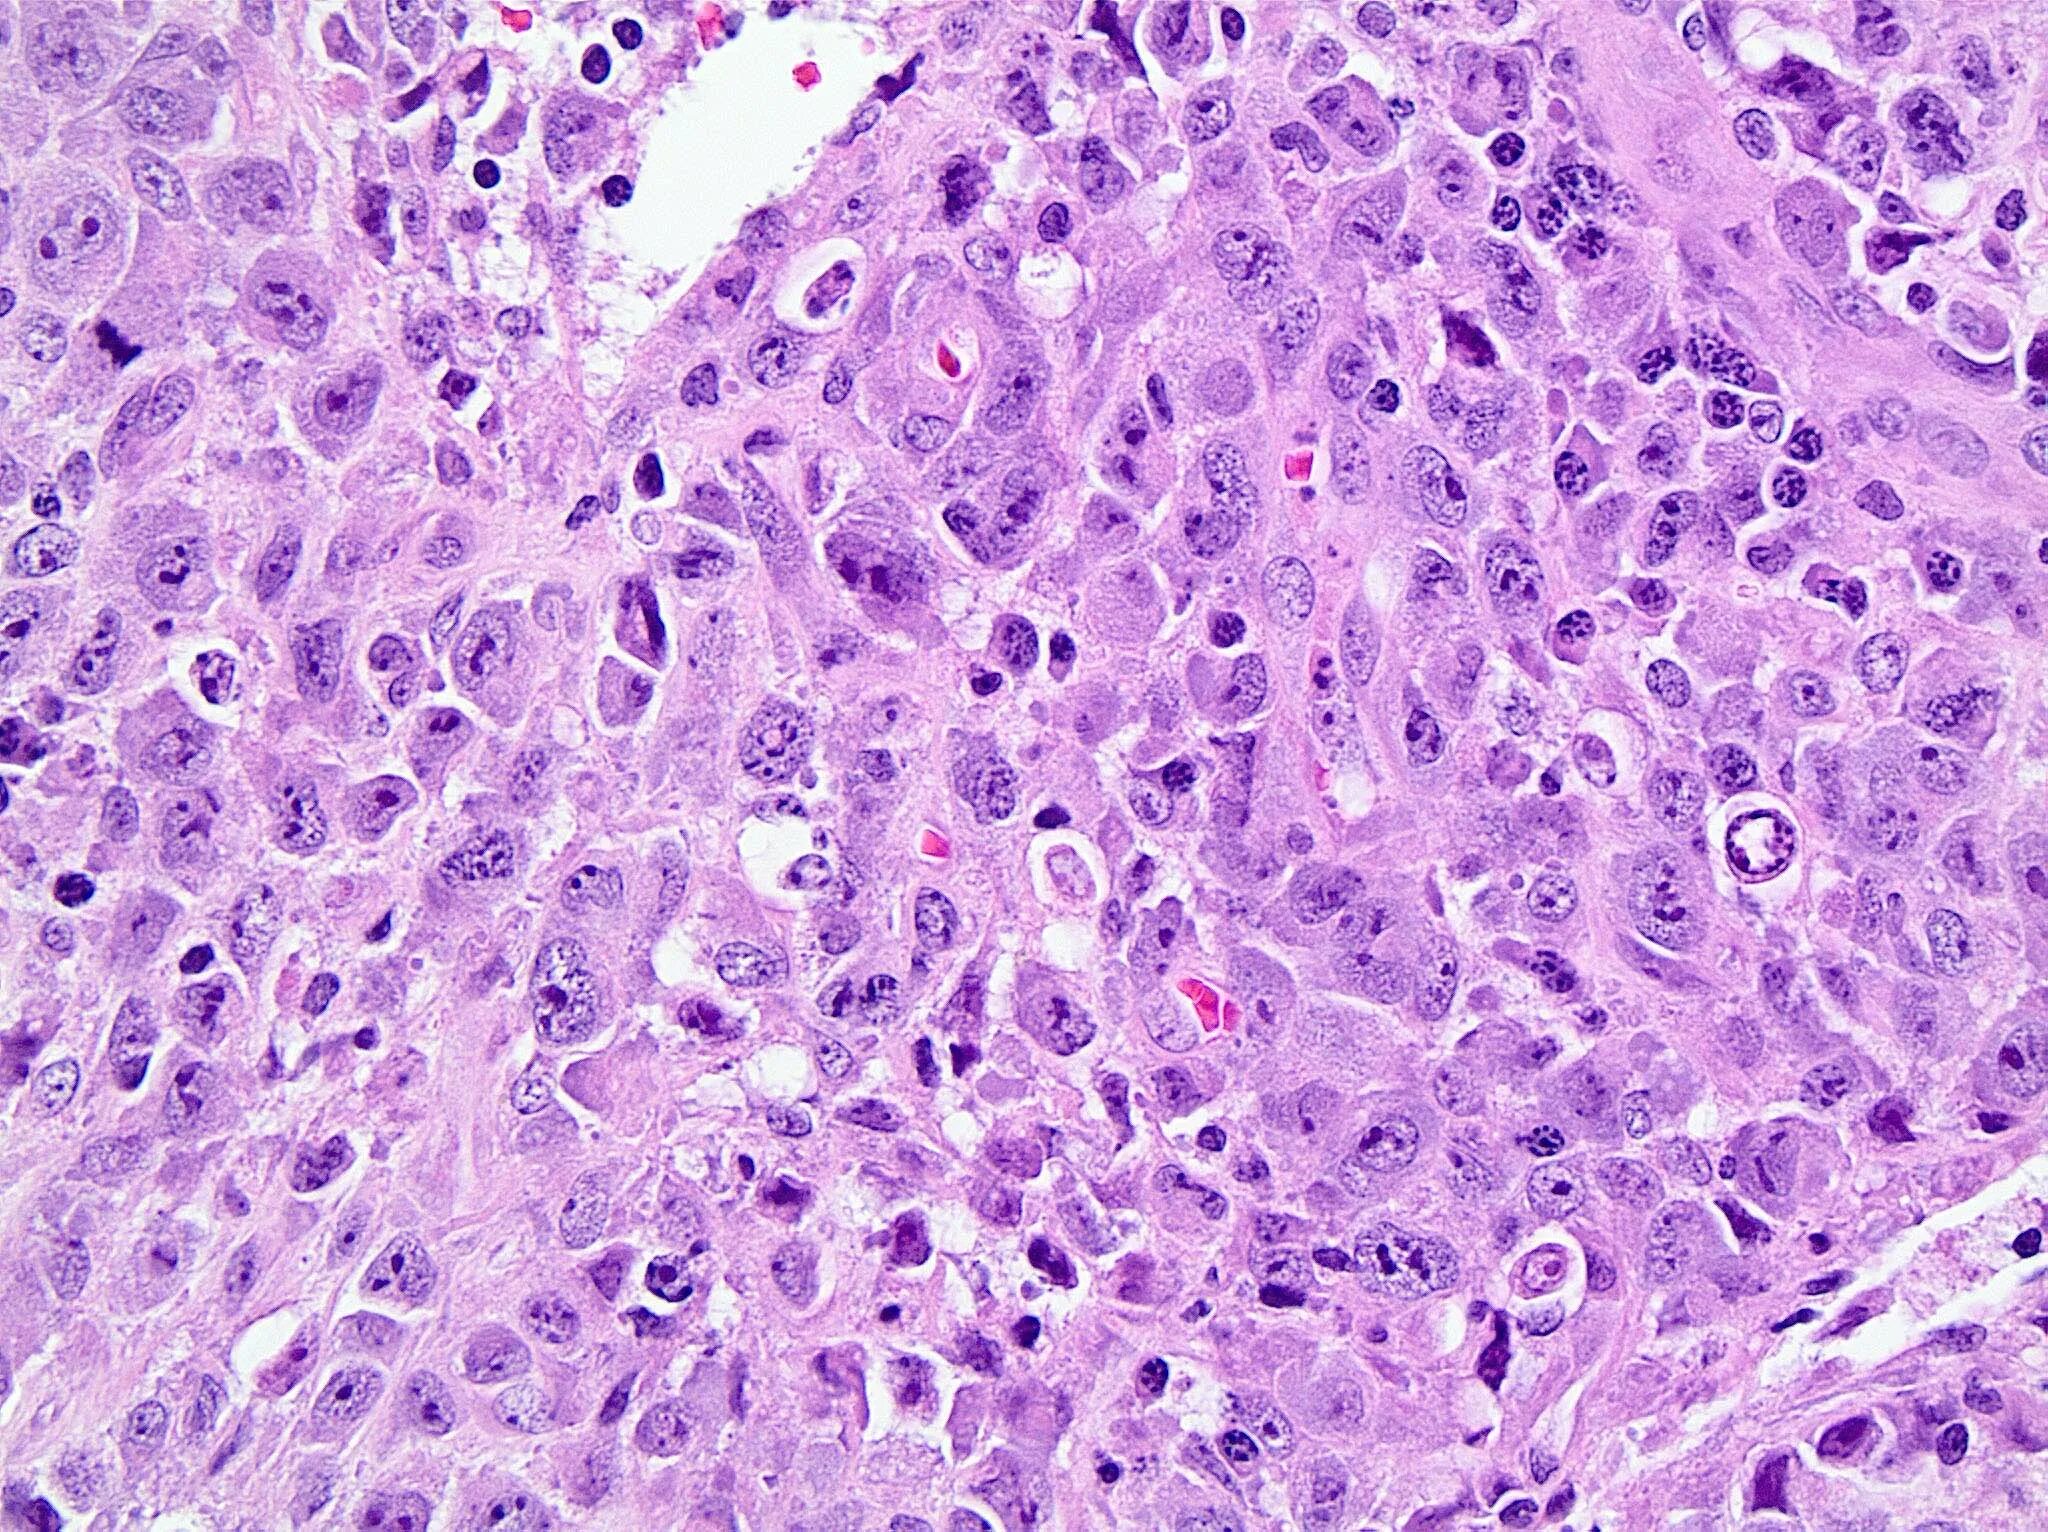

Гистологические варианты